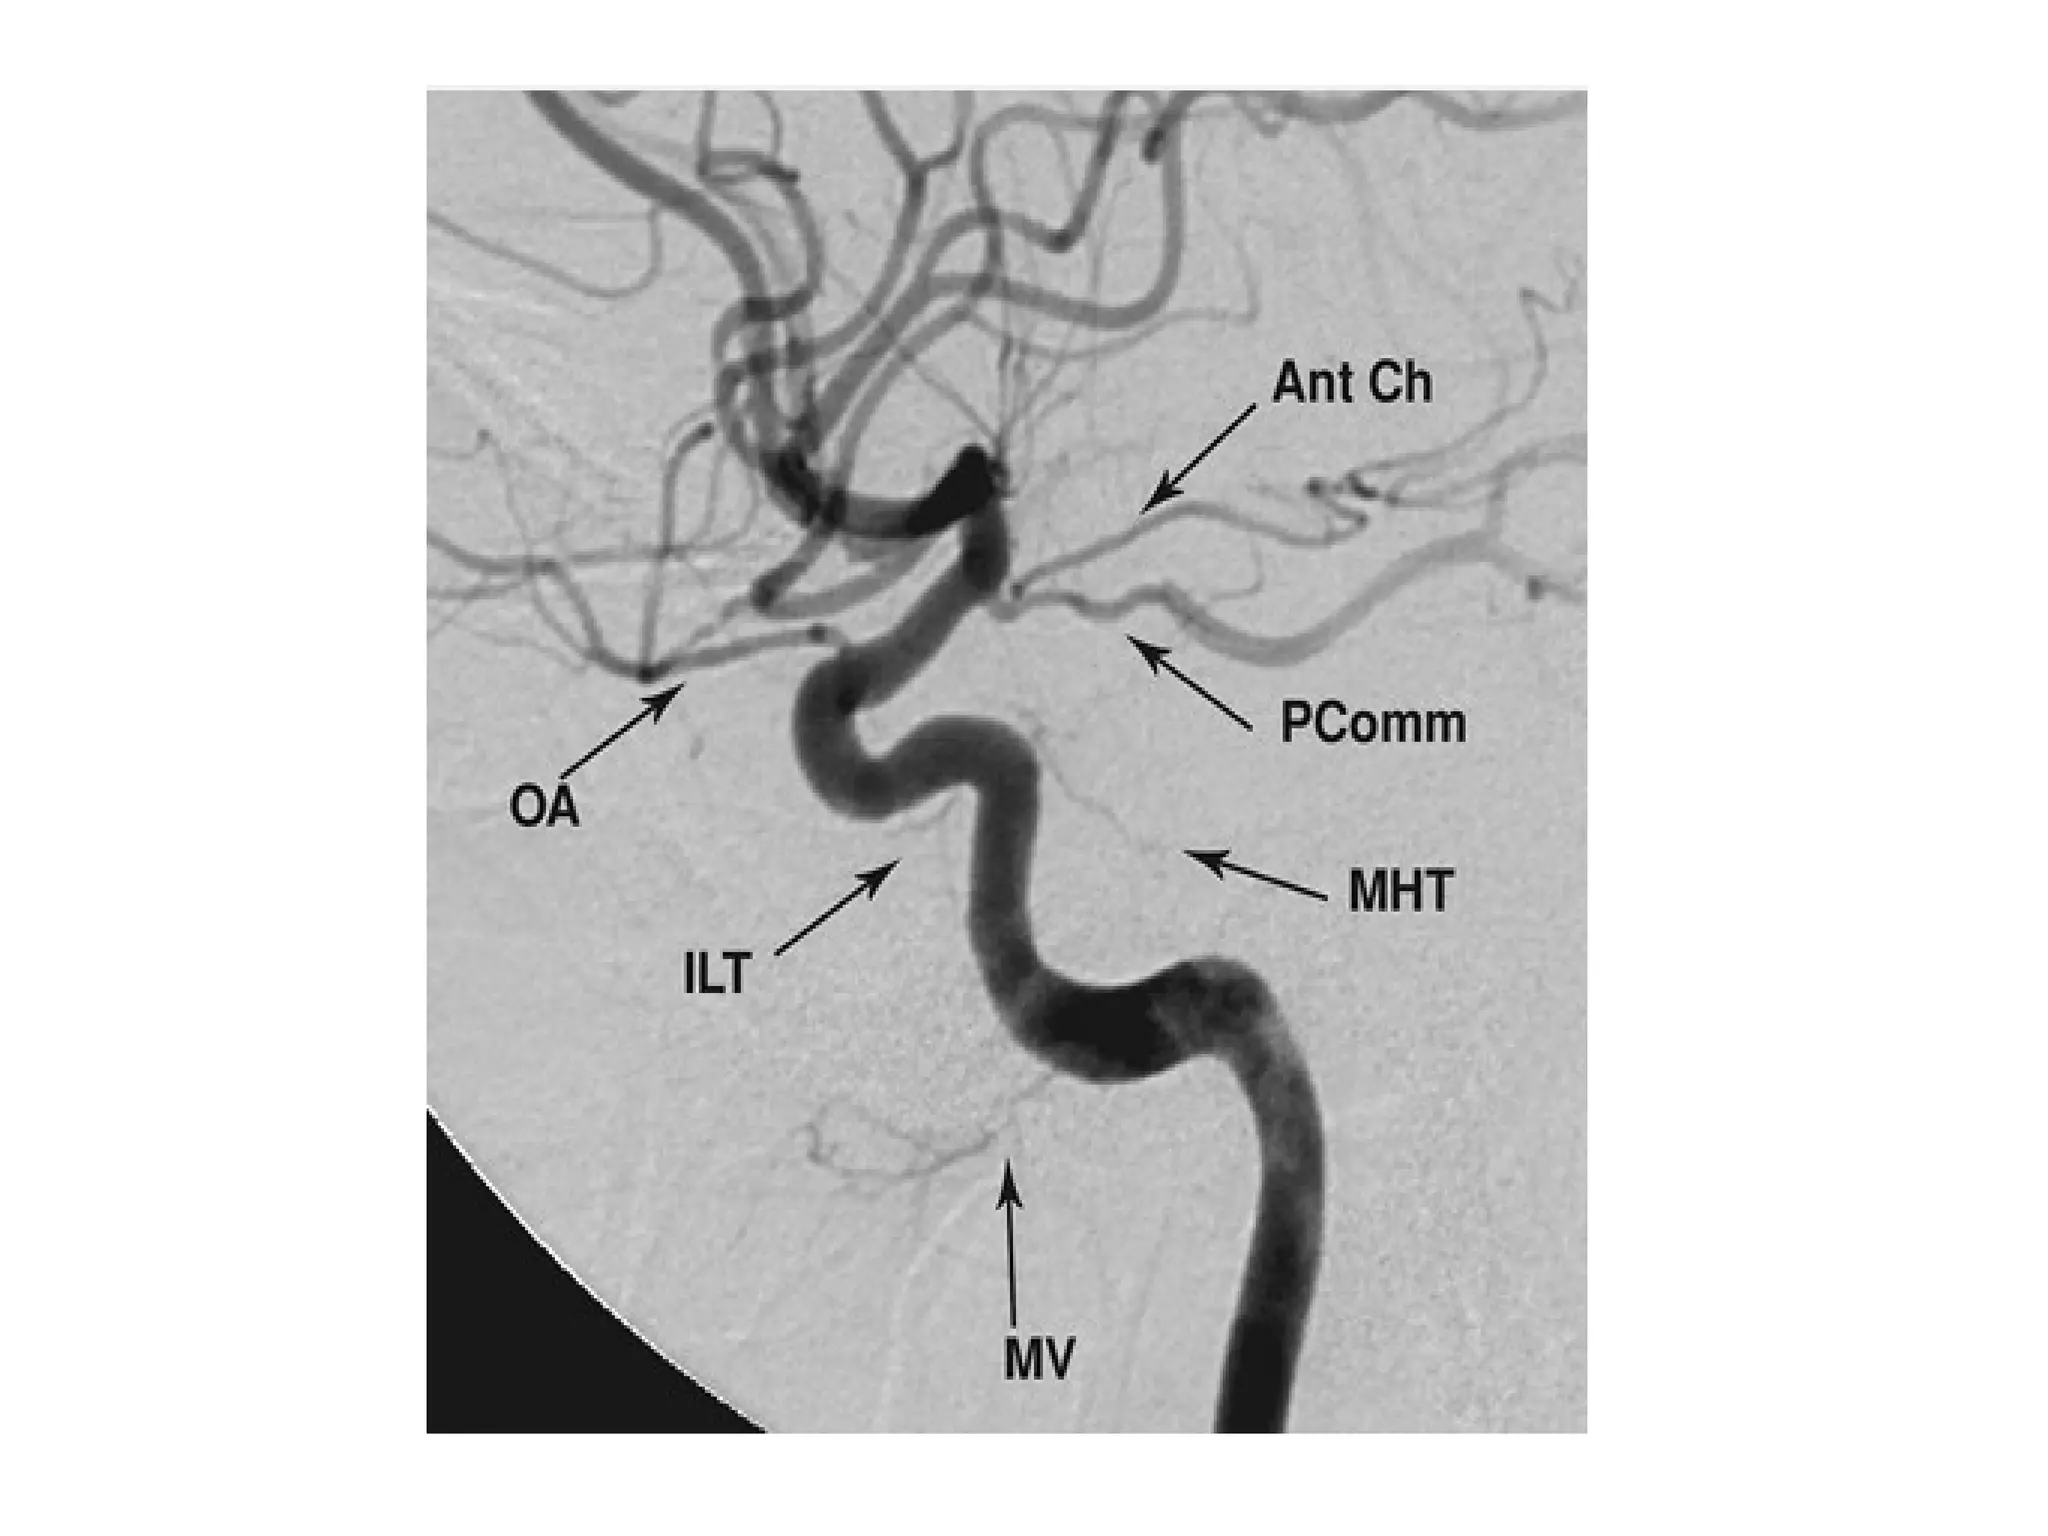

1-Internal Carotid Artery :

-Cervical (C1) : doesn’t branch within the neck

-Petrous (C2) : fixed to bone as the ICA enters the skull

base , so a cervical carotid dissection is unlikely to

extend intracranially

-Lacerum (C3) : no branches

-Cavernous (C4) :

*Meningohypophyseal trunk arises from the

cavernous carotid to supply the pituitary , tentorium

and dura of the clivus

*Inferolateral trunk also arises from C4 to supply the 3rd

, 4th

& 6th

cranial nerves as well as the trigeminal

ganglion

-Clinoid Segment (C5) : the carotid rings are two dural rings that

mark the proximal & distal portions of the clinoid segment of

the ICA , the carotid rings prevent an inferiorly located

aneurysm from causing intracranial SAH with rupture

-Supraclinoid (C6-C7) : gives off several key arteries :

2-PCOM :

-Is an anastomosis to the posterior circulation

-A fetal PCA is a variant supplied entirely by the ipsilateral ICA

via an enlarged PCOM

3-Anterior choroidal artery :

-Supplies several critical structures , despite its small size , it

supplies the optic chiasm , hippocampus and posterior limb of

the internal capsule

Ophthalmic artery

Lateral projection of a left common carotid artery injection that displays the

order of branching in the intracranial carotid including 1: ophthalmic , 2:

posterior communicating , 3: anterior choroidal and 4: anterior cerebral

arteries